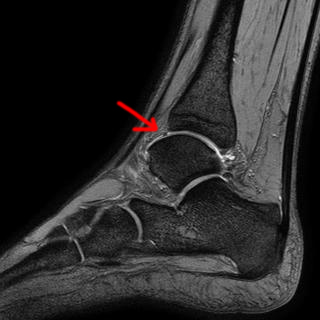

ich bin nun doch am Freitag endlich unter ein MRT gekommen. Der Befund steht noch aus, aber ich habe mal geraten. Was meint Ihr könnte das ein Knorpelschaden sein? Ich erwarte keine "wasserfeste" Diagnose. Nur eine Überbrücking bis ich am Freitag dann den Termin beim Arzt habe :)

Es würde jedenfalls gut mit der Stelle passen von der so ca der Stich kommt.